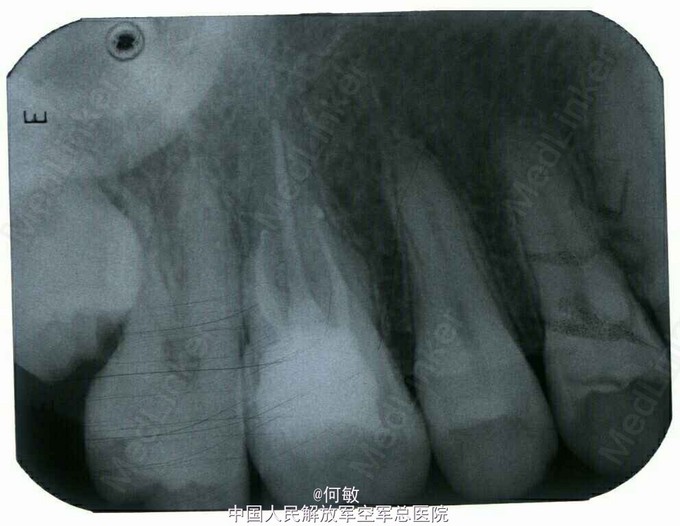

检查:颌面部左右基本对称,开口度及开口型正常。16合面及远中见龋损,龋洞内大量嵌塞食物,腐质较多,探痛明显,叩痛(—),无明显松动,牙龈无明显红肿。冷测引发疼痛,疼痛持续数分钟后缓解。 X线示:16远中低密度影像近髓,根尖区未见明显异常。

诊断:16慢性牙髓炎 治疗计划:16根管治疗后冠修复 治疗:1. 16阿替卡因局麻下,去腐未净露髓,于穿髓孔处置非砷慢失活剂,氧化锌水门汀垫底,邻面成形系统下,玻璃离子水门汀修复牙体远中壁及充填颌面。嘱勿用患牙咬物。 2.主诉:右上后牙上次治疗后无不适。 检查:16暂封物在,叩痛(—),牙体无松动,牙龈无明显红肿。 处置:16橡皮障下去除暂封物,去净腐质,开髓,揭净髓顶,降牙合,探及颊侧近远中和腭侧各一个根管口。直接+间接拔出残髓,超声扩大根管口,10号C锉疏通根管,干燥根管,电测工作长度WL:MB=19mm,DB=18.5mm,P=19mm。EDTA下,手扩至20#,PROTAPER镍钛根管锉预备根管至F2,CR冲洗+超声荡洗根管交替进行,复测根长同前。隔湿,干燥根管,封CP棉捻x3, 氧化锌水门汀+玻璃离子水门汀暂封。嘱勿用患牙咬物。 3.主诉:右上后牙上次治疗后无不适。 检查:16暂封物在,叩痛(—),牙体无松动,牙龈无明显红肿。 处置:16橡皮障下去除暂封物,取出棉捻x3,CR冲洗并干燥根管,复测工作长度同前:MB=19mm,DB=18.5mm,P=19mm。进口根充糊剂+6锥度25号、35号牙胶尖根充+热牙胶垂直加压回填至根管口,氧化锌水门汀垫底,玻璃离子水门汀暂封,术后拍片示:16根充恰填。嘱勿用患牙咬物。 建议:16冠修复